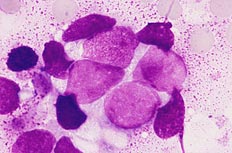

| [骨髄×1000.MG染色] 集塊細胞は18μm大でクロマチンは繊細網状である. |

[骨髄×400.MG染色] 集塊細胞は結合性がうかがえる. |

| [骨髄×1000.MG染色] 集塊細胞は大小不同もみられ、クロマチンは繊細から粗網状がみられる. PO染色に陰性である. |